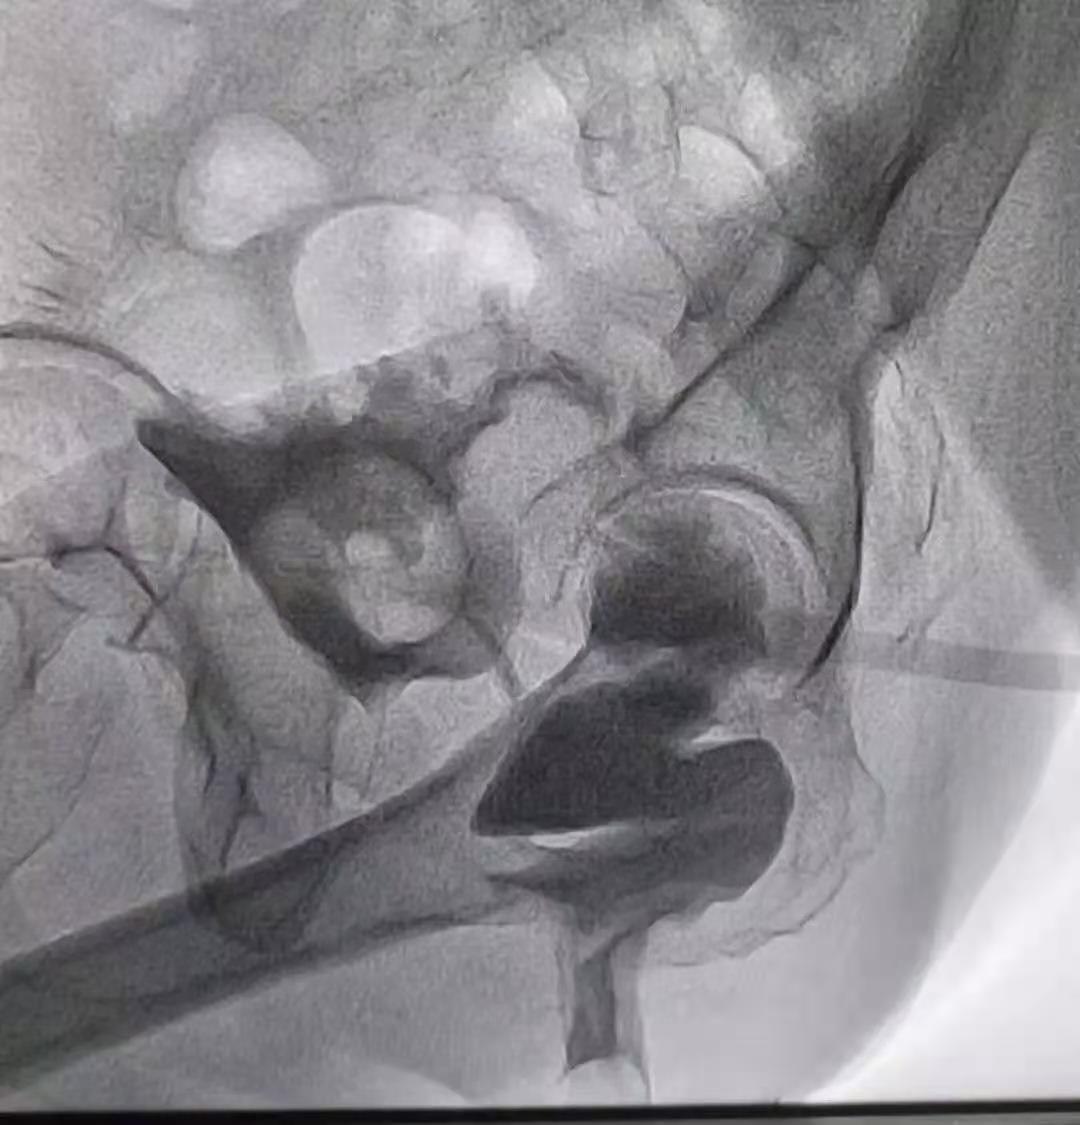

1、X光检查

在一段时间内有症状复发的患者可能需在饮用钡液后接受胃和小肠的 X 光检查(称为上消化道 [GI] 系列),或在钡灌肠后接受 X 光检查(称为钡灌肠)。新型方法包括 CT 小肠造影或磁共振小肠造影。另一种小肠评估方法是视频胶囊内镜检查。